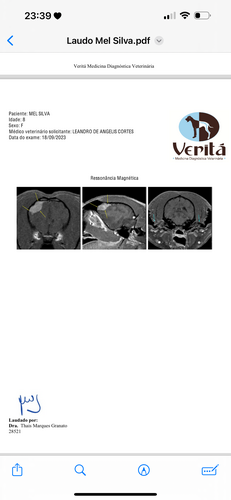

Olá eu sou a Priscila , dona da Mel , essa fofura aí da foto , há alguns meses foi diagnosticada com um tumor no cérebro chamado meningioma , ela precisa urgente de uma cirurgia para remoção do tumor ! Nos ajude a dar qualidade de vida e um tratamento digno a nossa Mel !qualquer quantia é bem vida, a cirugia é bem cara mais fará com que a mel sobreviva a doença ! Precisamos arrecadar os 16.000 para a cirurgia! Nos ajude , Lambeijos da Mel ❤️